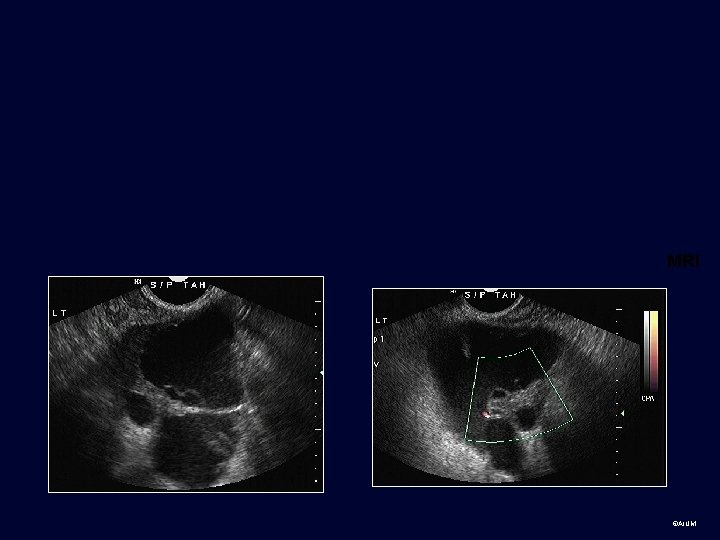

Group 3 ©AIUM

©AIUM